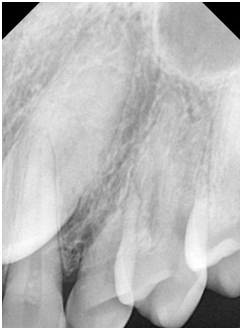

A 40-year-old female patient presented to the private practice of one of the authors with a chief complaint of unaesthetic concern of her deciduous teeth #63 (Figure 1). According to the clinical examination and x ray, tooth #23 was non erupted and was retained on the palatal region Tooth #63 presented as a dark tooth with a non-carious cervical lesion at the vestibular aspect and an obvious smaller size (Figure 2).